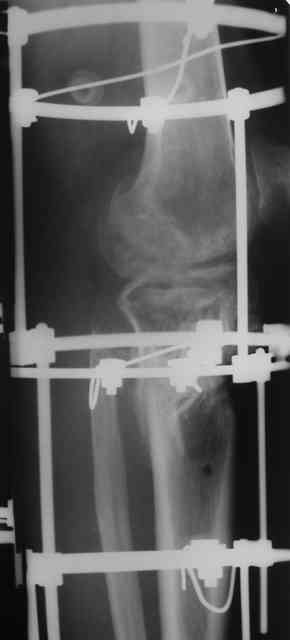

Р-граммы за март и апрель

Р-граммы и фото за 4.05.2007 - 7-е сутки после операции.

Ход операции - линейным разрезом по передней поверхности голени обнажена зона ложного сустава большеберцовой кости. От кости отсепарованы медиально м/ткани. Из зоны ложного сустава убраны рубцовые ткани, мобилизован дистальный отломок. По передней поверхности удалены два осколка, связанных грануляциями. Произведено удаление грануляционной ткани из проксимального отломка (на вид сине-серого цвета), "чистого" гноя не было. Затем произведено наложение аппарата и репозиция отломков. По передне-медиальной поверхности образовался дефект до 4х2х2 см + полость в проксимальном отломке. Удаленные осколки очищены от грануляций, уложены в место дефекта, зажаты между отломками. После иссечения раны по передней поверхности, находящейся рядом с операционной раной, последняя ушита с большим натяжением.

Перелом мыщелка сросся. Проксимальный отломок очень порозный.

Аппарат видел, репозиции не заметил. О "наложенном" аппарате: спицы в проксимальном отломке б\берцовой кости проведены очень низко, и опять только две, как и в первом аппарате. Почему только одна спица в дистальном парафрактурном кольце? Проксимальная база на бедре должна улучшить стабильность проксимального фрагмента tibia? Ничего подобного двумя спицами в одной базе при таком длинном рычаге вы не добьетесь, а вот совсем потерять движения в коленном суставе они почти гарантируют.

О репозиции: мыщелок сросся и слава Богу, но основные отломки фиксированы в вальгусном положении, собственно как и было, это критично. В чем состояла репозиция?

Согласен с оценкой Алексея. Секцию на бедро не нужно, на ровном месте сформируется контрактура коленного сустава. В проксимальный эпиметафиза большеберцовой ввели бы 4-5 спиц с упорами, в том числе в виде петли, и хватило бы.